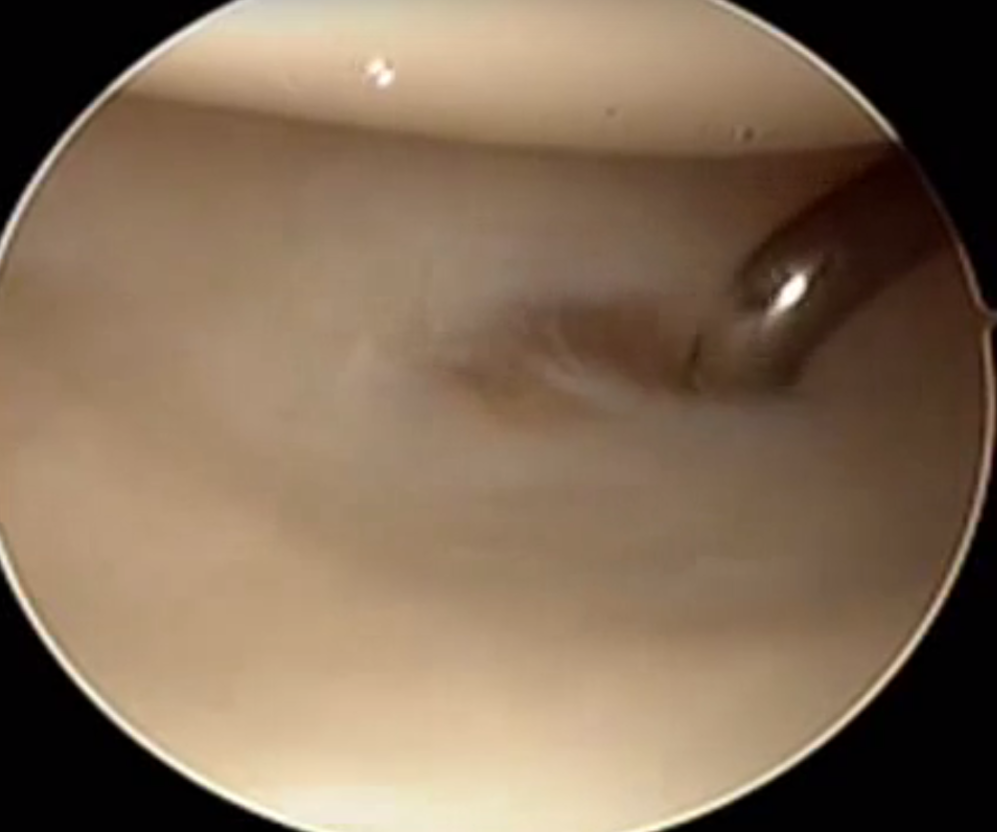

Technique arthroscopic repair

Ulna / foveal sided TFCC tear on arthroscopy

Technique

- viewing via 3-4 portal

- instrumentation via 6R +/- 6U portal (either side of ECU)

- pass outside in and suture over capsule

- suture anchor repair

- drill hole in ulna